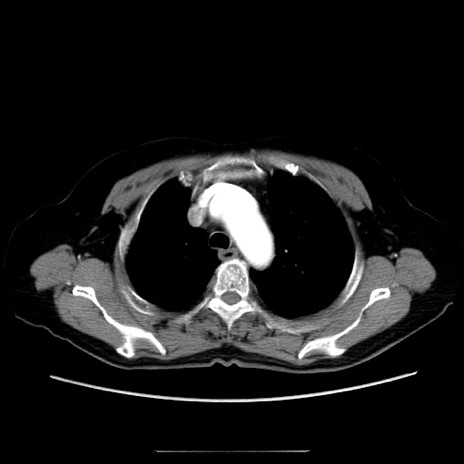

【症例】70歳代女性

【主訴】お腹が張る

【現病歴】1週間くらい前から腹部膨満の自覚あり。昨日夜から増悪したため、本日救急外来受診。

【身体所見】意識清明、BT 36.5℃、BP 165/106mmHg、HR 80bpm、SpO2 98%、腹部:膨満、軟、自発痛・圧痛なし、触診にて不快感あり、腸蠕動音:減弱

【データ】WBC 12600、CRP 1.04